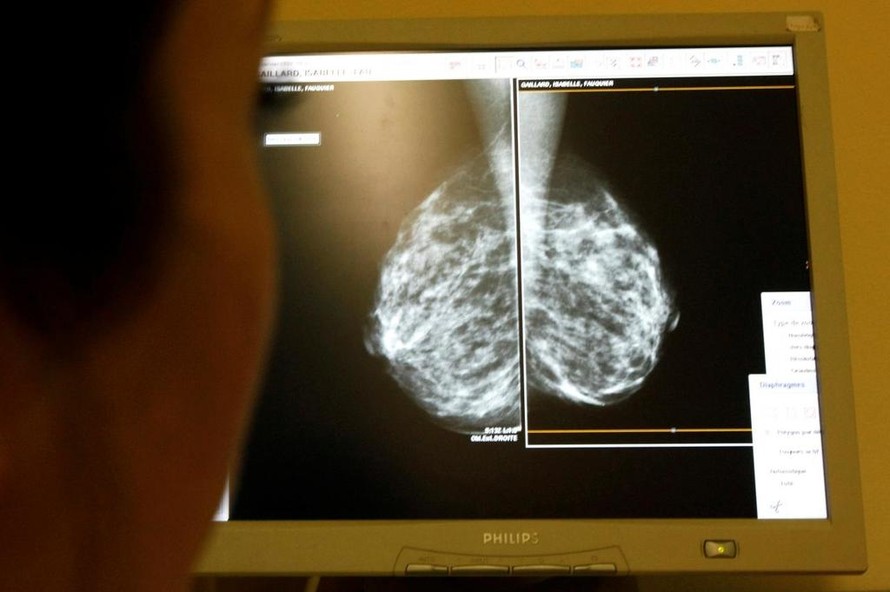

Công nghệ AI giúp nhanh chóng phát hiện ung thư vú

(Ngày Nay) - Một hệ thống trí tuệ nhân tạo của Google đã chứng minh được khả năng của mình trong việc phát hiện phụ nữ nào bị ung thư vú dựa trên hình chụp X quang tuyến vú.

Nghiên cứu trên mới được công bố trên tạp chí Nature vào thứ Tư, cho thấy trí thông minh nhân tạo (AI) có khả năng cải thiện độ chính xác của sàng lọc ung thư vú, căn bệnh ảnh hưởng đến 1/8 phụ nữ trên toàn cầu.

Các bác sĩ X quang có khả năng bỏ lỡ khoảng 20% mầm bệnh ung thư vú khi xem xét hình chụp X quang tuyến vú, Hiệp hội Ung thư Mỹ cho biết, trong khi một nửa số phụ nữ được kiểm tra trong khoảng thời gian 10 năm có kết quả dương tính giả.

Những phát hiện của nghiên cứu, được phát triển với công ty nghiên cứu trí tuệ nhân tạo DeepMind AI của công ty mẹ Google là Alphabet, đã thể hiện một bước tiến lớn trong khả năng phát hiện sớm bệnh ung thư vú, theo các tác giả của công trình nghiên cứu.

Nhóm nghiên cứu, bao gồm các nhà nghiên cứu tại Đại học Hoàng gia London và Dịch vụ Y tế Quốc gia Anh, đã dựa vào hệ thống AI của Google để xác định mầm bệnh ung thư vú trên hàng chục ngàn hình ảnh chụp X quang tuyến vú của các phụ nữ khác nhau.

Nghiên cứu cho thấy hệ thống AI có thể xác định bệnh ung thư với độ chính xác tương tự như các chuyên gia X quang, đồng thời giảm từ 1,2-5,7% kết quả dương tính giả ở các bệnh nhân tại Anh và Mỹ.

Trong một thử nghiệm riêng biệt, nhóm nghiên cứu đã cho hệ thống AI đọ sức với 6 bác sĩ X quang và kết quả cho thấy trí tuệ nhân tạo tỏ ra vượt trội hơn các con người khi phát hiện chính xác ung thư vú.